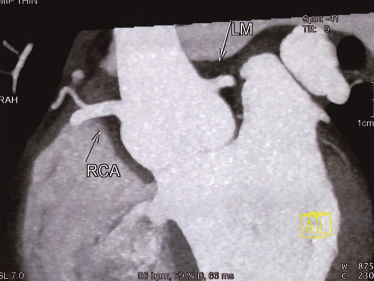

术前CT全方位判断室缺位置、形态及大小